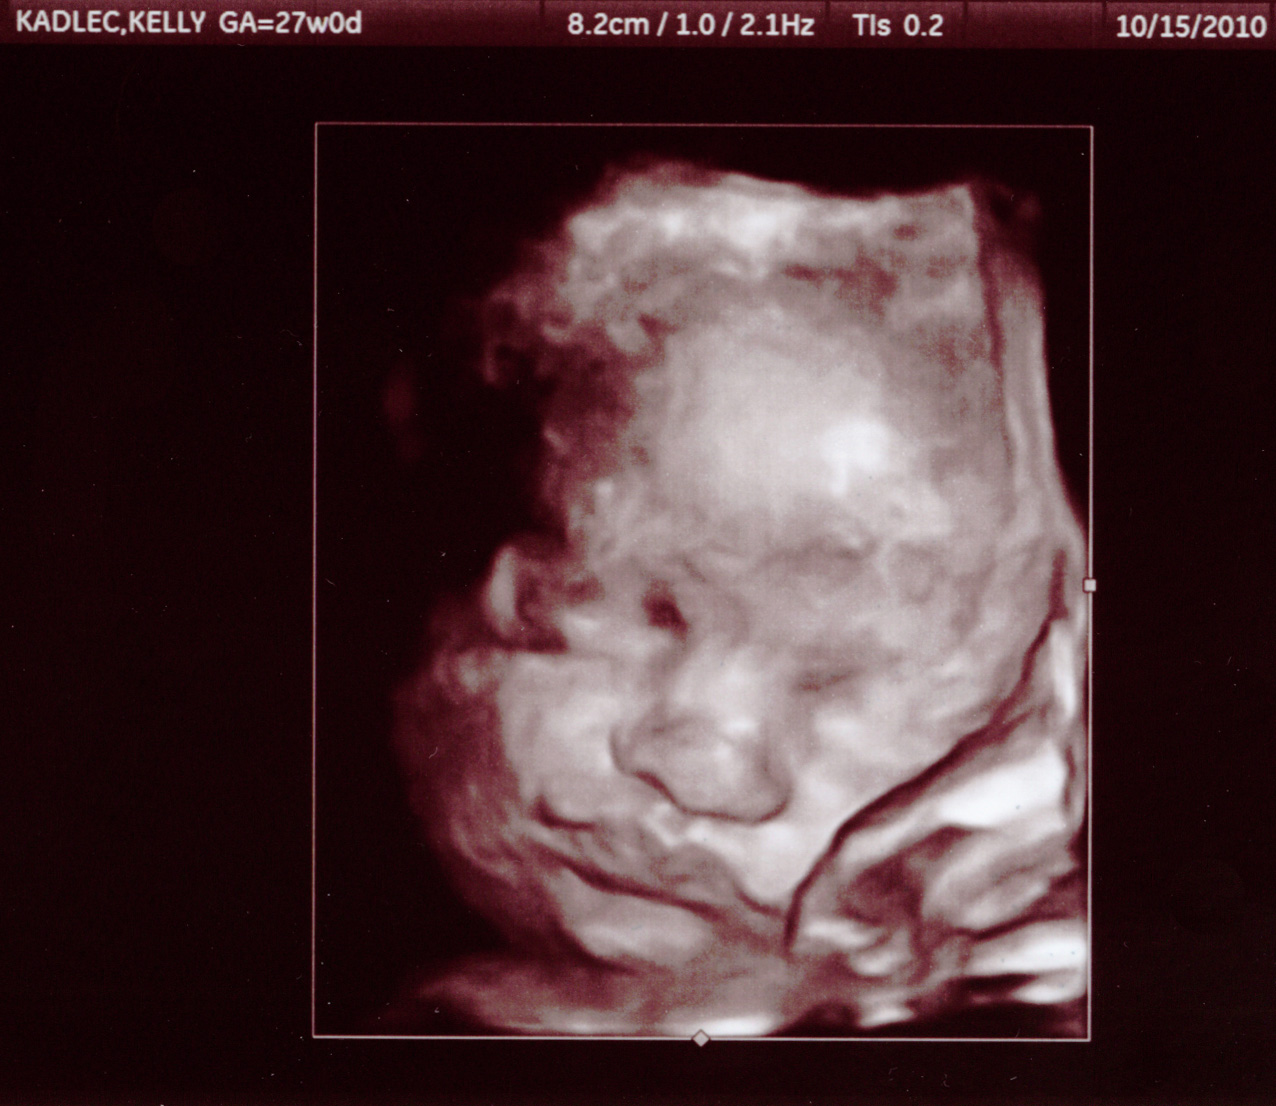

15 October 2010

Here are some pictures from our 27 week appointment.

He's a little over 2lbs.